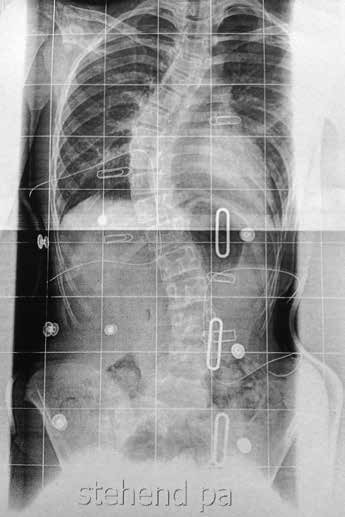

Ausgangspunkt für die korrekte Beurteilung einer Skoliose ist eine Ganzwirbelsäulenaufnahme (GWS) im Röntgen. Mittlerweile hat sich an unserer Klinik eine Aufnahme in p.-a.-Richtung etabliert, um bei Mädchen die Ovarien durch Abdeckung des Os ilium zu schützen (Abb. 4). Anhand der GWS kann der Fachmann die wichtigen Parameter wie die Lotabweichung, das Ausmaß der Skoliose, eine eventuell vorhandene und unbedingt zu beachtende Beinverkürzung und das Risser-Stadium beurteilen.

Ebenso ist, zumindest zu Beginn der orthetischen Versorgung, eine Beurteilung des sagittalen Profils im Röntgen erforderlich. Eine alternative Rasterstereografie ist nach Ansicht des Autors im Korsettbau dagegen wenig hilfreich, auch wenn sie dem Arzt im weiteren Behandlungsverlauf Aussagen über einen Progredienzausschluss liefern kann (Abb. 5).